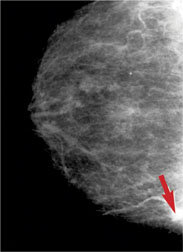

It’s been medical gospel for years: All women 50 years and older–and younger women in high-risk groups for breast cancer–should undergo mammography once every year or two. But recent reviews of the screening procedure have disagreed about whether routine mammograms help prevent breast cancer deaths. In the face of that scientific uncertainty, what’s a woman to do? There’s even disagreement among doctors and the groups that make policy recommendations.

The screening procedure has a variety of financial and psychological costs, although the X-ray exposure of a mammogram isn’t considered a significant danger. Mammography screening’s overall expense in the United States–including follow-up procedures–runs into the billions of dollars. During screening, 5 to 10 percent of mammograms show potential abnormalities, requiring doctors to order additional mammograms, ultrasound imaging, biopsies, and other tests. However, about 97 percent of women in their 40s and about 86 percent of women age 50 and over who have a suspicious initial mammogram turn out not to have breast cancer.